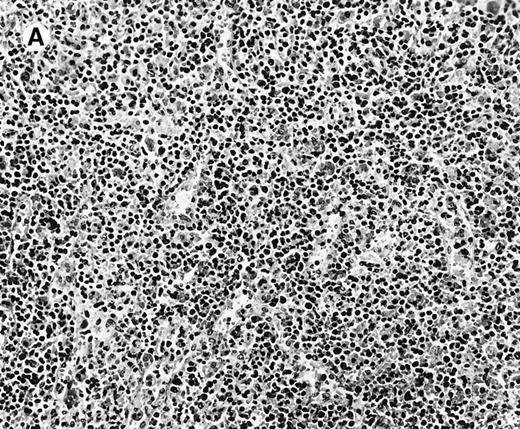

All cases showed essentially similar histologic findings in the liver and spleen. The splenic white pulp was inconspicuous to markedly depleted, whereas the sinusoids showed a prominent lymphoid infiltration (Figure 1A). There was striking hemophagocytosis within the splenic sinusoids (Figure 1B). The infiltrating lymphocytes were small and lacked significant cytologic atypia (Figure 1B). Immunoblasts and plasma cells were not prominent. The liver had prominent portal as well as sinusoidal infiltrates of small lymphocytes morphologically identical to those noted in the spleen (Figure 2). There was intracellular and intracanalicular cholestasis, steatosis, and focal necrosis. Hemophagocytosis was present within the sinusoids. In case 5, the spleen showed extensive areas of necrosis mainly in the perifollicular and periarteriolar lymphoid sheaths of the white pulp with the presence of immunoblasts reminiscent of IM.

Histologic findings in spleen.

(A) Section of spleen from case 2 shows depletion of white pulp and prominent sinusoidal small lymphoid infiltrates (hematoxylin and eosin, × 200). (B) The lymphocytes lack significant cytologic atypia. There is marked hemophagocytosis (hematoxylin and eosin, × 600).